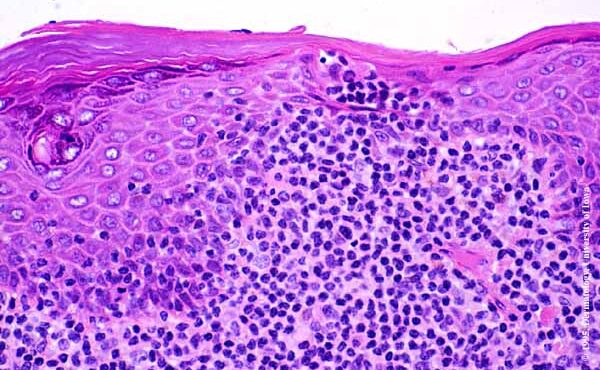

Parapsoriasis Large-plaque = نظير الصدف كبير اللويحات Parapsoriasis There are three entities described as parapsoriasis: small-plaque parapsoriasis, large-plaque parapsoriasis, and parapsoriasis variegata. Large-plaque parapsoriasis and parapsoriasis variegata are best considered as early stages of cutaneous T-cell lymphoma/mycosis fungoides. The small-plaque parapsoriasis is also known as xanthoerythrodermia perstans of Crocker and as digitate dermatosis . Pink-to-yellow, slightly scaly, oval or elongated, […]